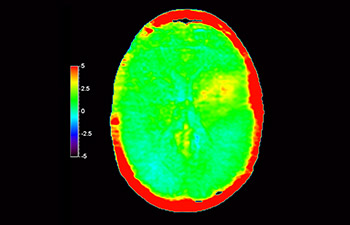

3D APT (Amide Proton Transfer) is a unique, contrast-free, brain MR imaging method addressing the need for more confident diagnosis in neuro oncology. 3D APT uses the presence of endogenous cellular proteins, to produce an MR signal that directly correlates with cell proliferation, a marker of tumoral activity. 3D APT can support trained medical professionals in differentiating low grade from high grade gliomas and, in differentiating tumor progression from treatment effect1.

Brain lesion

with 3D APT